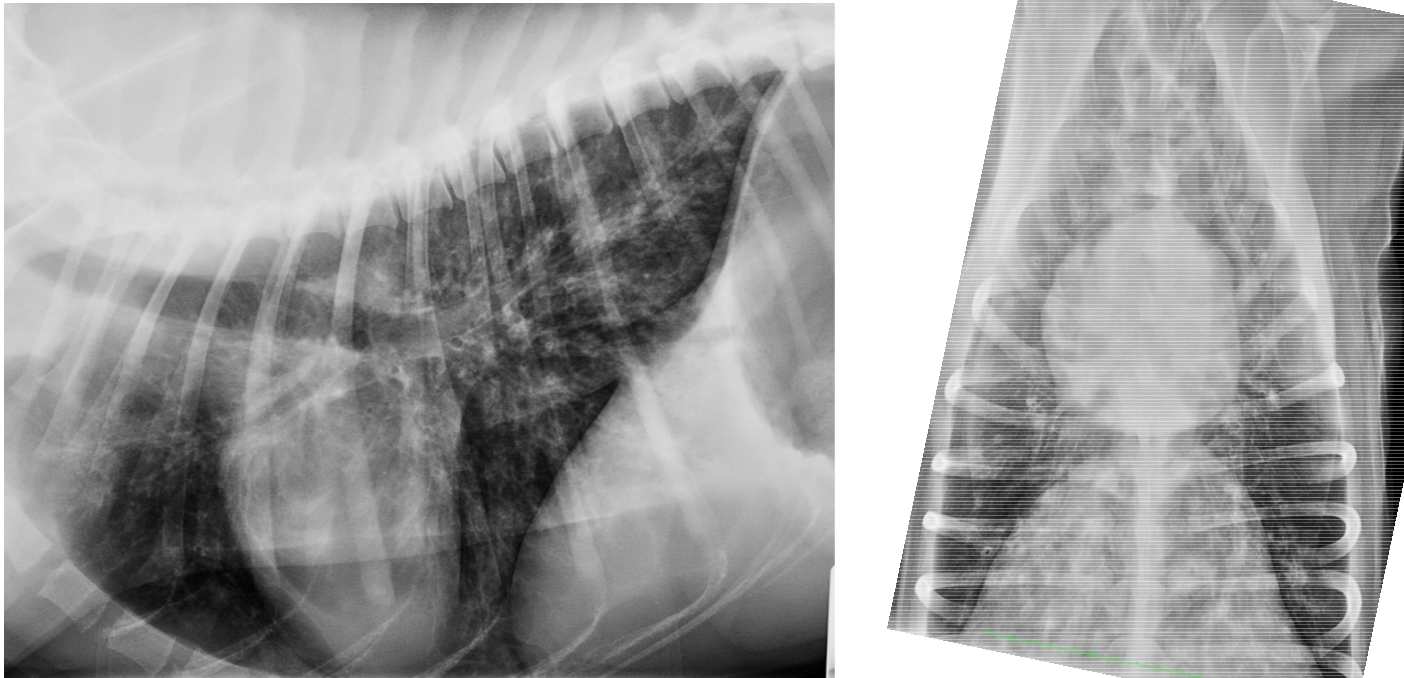

• what pattern can be seen here?

broncho-interstitial

• eosinophillic bronchopneumopathy is more common in dogs, with reactive eosinophilic airway disease occurring in cats. This typically occurs in young adults and can either have an acute or chronic presentation. These cases are usually coughing but you can also see weight loss. Radiographs show a diffuse broncho-interstitial pattern although can see alveolar patterns (can be dense infiltrates).

• Radiograph may show alveolar infiltrates

• In the early stages of the disease, a multifocal or peripheral alveolar pattern can be visualized. This pattern is associated with pulmonary granulomas or haemorrhage caused by A. vasorum. As the infection progresses, an interstitial pattern is seen throughout the lung parenchyma, along with pleural fissure lines.